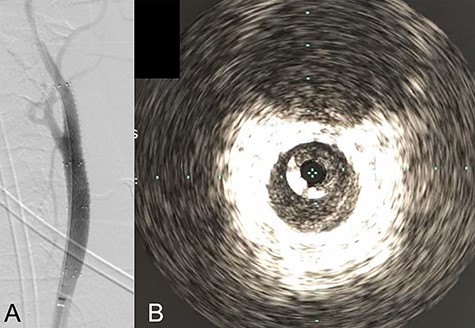

We performed CAS and started dual antiplatelet therapy 27 days after stroke onset to prevent further dissection and cerebral infarction recurrence. The dissection started 1.5-cm below the carotid bifurcation (Fig. 3A). An 8 fr guiding catheter (FlowGate2 Balloon Guide Catheter, Stryker, Fremont, CA, USA) was positioned at the proximal portion of the left CCA with a micro-guidewire (ASAHI CHIKAI Black, Asahi-Intecc, Nagoya, Aichi, Japan) crossing the dissected lesion. A distal protection device (SpiderFx Embolic Protection Device, Medtronic, Minneapolis, MN, USA) was deployed at the petrous portion of the ICA. IVUS was first advanced into the petrous ICA, and vessel wall imaging was performed by slowly withdrawing the device. IVUS imaging confirmed the existence of the dissection’s pseudo-lumen starting 1-cm proximal to the carotid bifurcation (Fig. 3C). IVUS provided the ICA and CCA diameters, which helped decide the most suitable stent (Fig. 3B and C). To adequately cover the dissection lesion, we placed two opened cell stents (Protégé, Medtronic, Minneapolis, MN, USA); one was an 8–6-mm tapered model with a length of 40 mm to cover the lesion from the distal CCA end to the proximal portion of ICA. Another was a 10-mm straight model with a length of 40 mm covering the CCA. Post-dilation was performed SterlingTM Balloon Dilation Catheter (Boston Scientific, Natick, MA, USA) with 5 × 20 mm covering both stents’ edges. The final angiography showed successful treatment with a smooth intra-arterial lumen (Fig. 4A). IVUS imaging showed sufficient stent coverage of the entire dissection lesion. It also confirmed a good expansion of the stent to the dissection area’s arterial wall with no plaque protruding the stents (Fig. 4B).

Angiography after stent placement showed favorable patency of the carotid artery with a smooth intra-arterial lumen (A). IVUS performed after stenting confirmed an excellent expansion of the stent to the dissection lesion’s arterial wall with no plaque protruding the stents (B).